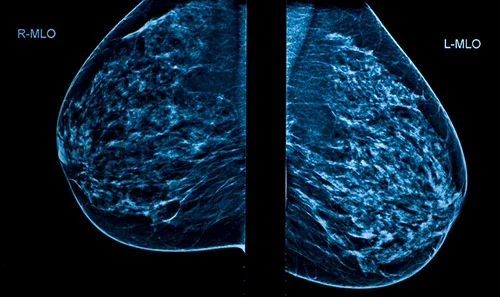

Mammografia to badanie przesiewowe w profilaktyce raka piersi | foto Medicover